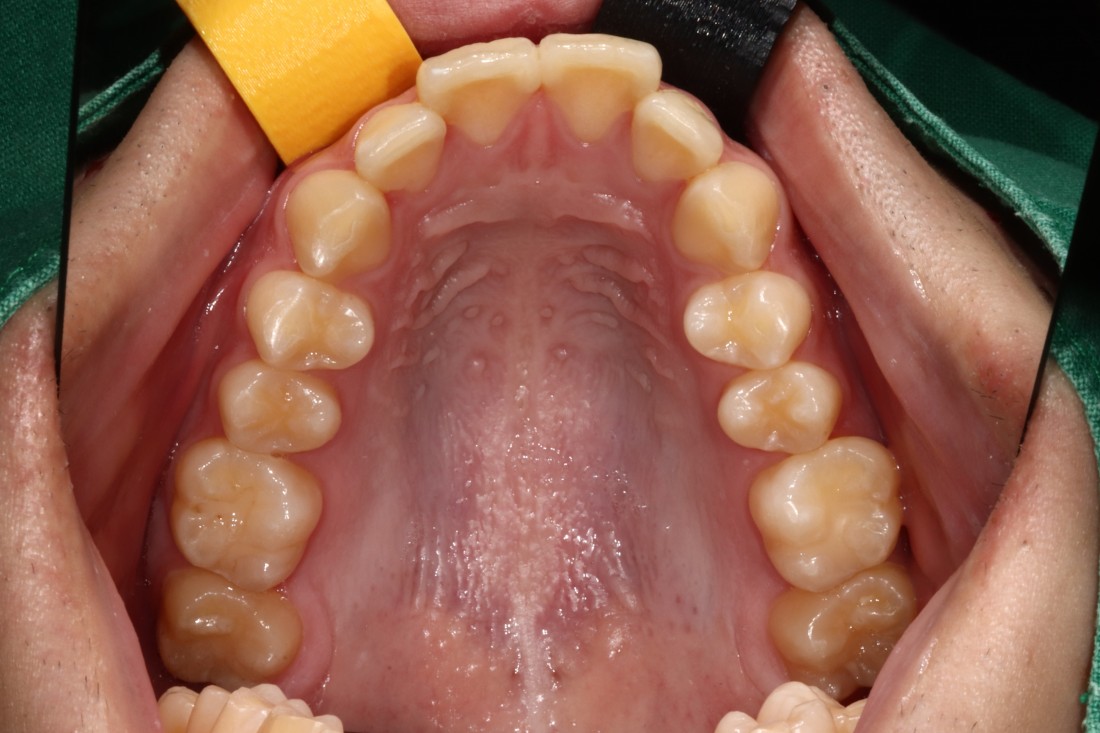

광주 개방교합 교정을 위해

방문해주신 30대 남성 환자분의

교정 전 사진입니다.

어금니를 맞닿게 하여서 입을 다물어도

윗니와 아랫니가 만나지 않는데요.